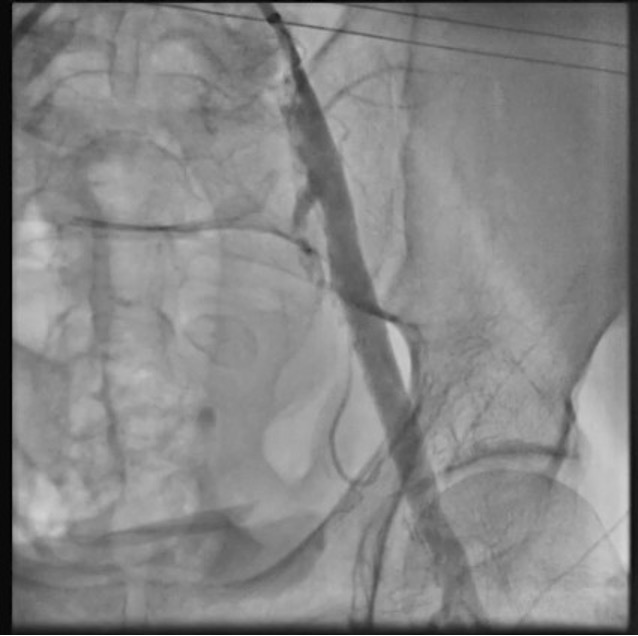

The patient was taken up for TAVR via a left common femoral artery (CFA) approach. The aortic valve was crossed (Figure 1A), and pre-dilatation was done using an 18-mm x 40-mm Mammoth balloon catheter (Meril Life Sciences) (Figure 1B). A 24.5-mm Myval transaortic valve (Meril Life Sciences) was introduced inside a Python expandable introducer sheath (Meril Life Sciences). However, the device could not be negotiated in the distal external iliac artery (EIA) due to calcium. The arrow in Figure 2A shows calcium in the distal EIA. The artery forceps depicts a marker for the distal end of the Python sheath. The sheath was withdrawn in the distal EIA; right CFA puncture was done and a 7F crossover sheath was placed. Intravascular lithotripsy (IVL) was done using a 7-mm x 60-mm IVL balloon; 30 pulses at 4 atm followed by 30 pulses at 6 atm were given (Figure 2B).